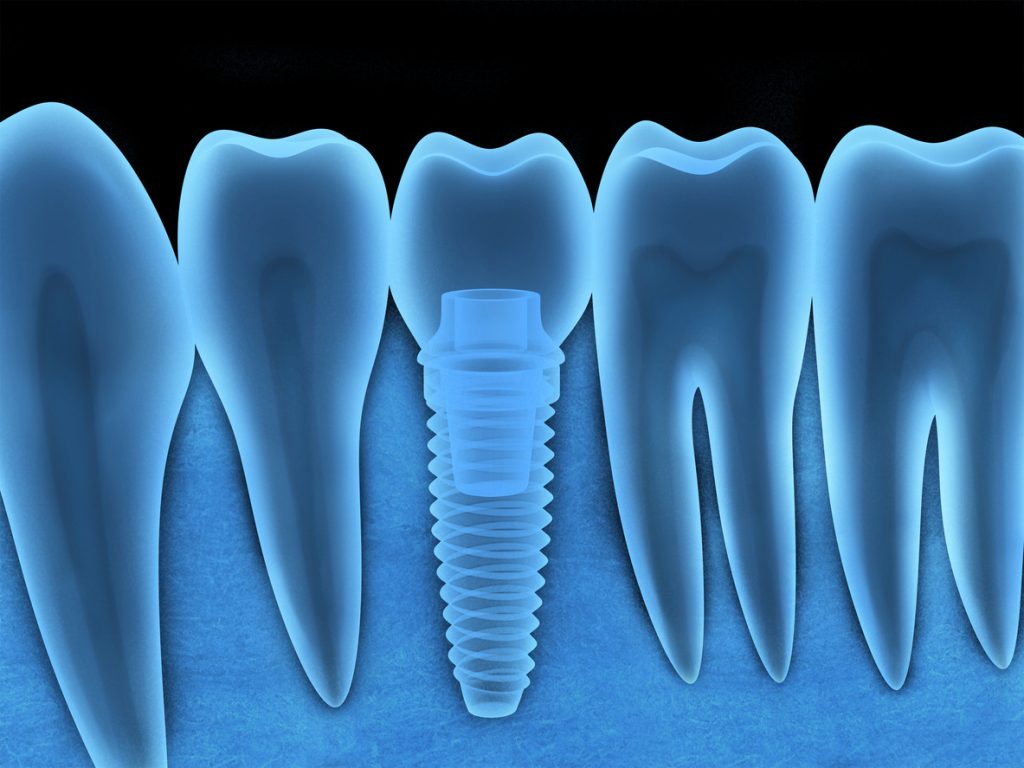

Dental Bone Loss Xray This allows the surgeon to place dental implants to replace and restore missing or lost teeth. Additional intraoral films might be helpful where. This allows the surgeon to place dental implants to replace and restore missing or lost teeth. Your dentist may assign a stage and a. A preorientation with respect to the expected bone loss is possible using panoramic radiographs. When evaluating the staging of periodontal disease, categorized on a scale from 1 to 4, it is essential to consider several. If you have significant bone loss, your dentist can use regenerative bone grafting to supplement the bone surrounding your teeth. This week is all about the basics of horizontal bone loss and vertical bone defects on radiographs. When identifying horizontal bone loss.

Dental Bone Loss Xray If you have significant bone loss, your dentist can use regenerative bone grafting to supplement the bone surrounding your teeth. When identifying horizontal bone loss. This week is all about the basics of horizontal bone loss and vertical bone defects on radiographs. This allows the surgeon to place dental implants to replace and restore missing or lost teeth. Additional intraoral. Dental Bone Loss Xray.

Jaw Bone Regeneration Sparta, NJ Perio Implant Specialists Dental Bone Loss Xray This week is all about the basics of horizontal bone loss and vertical bone defects on radiographs. If you have significant bone loss, your dentist can use regenerative bone grafting to supplement the bone surrounding your teeth. This allows the surgeon to place dental implants to replace and restore missing or lost teeth. Your dentist may assign a stage and. Dental Bone Loss Xray.